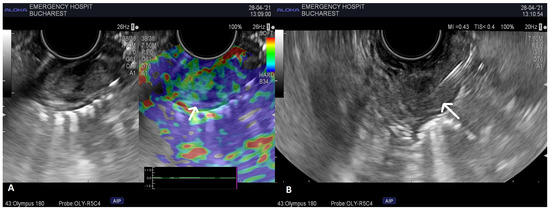

2. Case Report 1